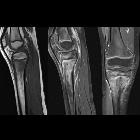

Plain radiograph

- lytic lesion often in an oval configuration that is oriented along the long axis of the bone

- surrounded by a thick dense rim of reactive sclerosis that fades imperceptibly into surrounding bone

- lucent tortuous channel extending toward growth plate prior to physeal closure (pathognomonic)

- periosteal new-bone formation +/- adjacent soft-tissue swelling

- may persist for many months